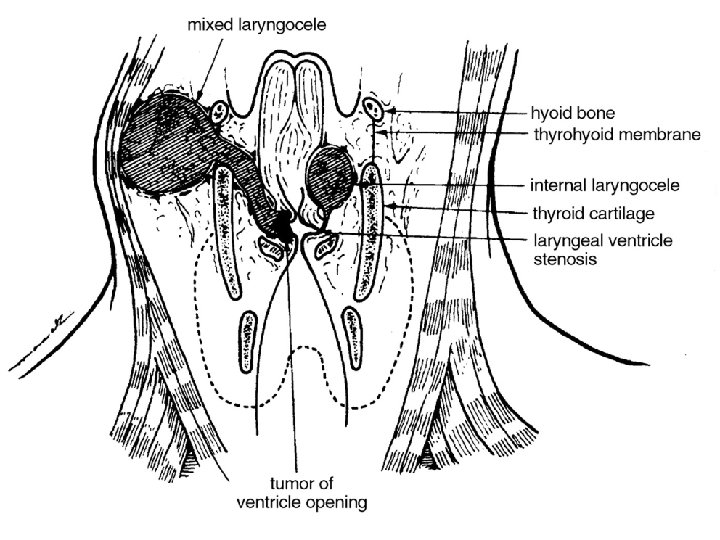

CLASIFICACIÓN ¡LARINGOCELE Relación con la membrana tirohioidea en: ¡Interno: ¡Saco aéreo limitado al área de la banda ¡Se extiende posterosuperior al pliegue aritenoepiglótico (dentro del cartílago laríngeo) ¡Externo: ¡Se extiende cefálico y protruye hacia membrana tirohiodiea ¡Sobrepasa el cartílago tiroides ¡Combinado (Puede protruir al examen físico durante valsalva)

¡ A, Normal larynx B, internal laryngocele C, external laryngocele D, combined laryngocele E, lateral saccular cyst F, anterior saccular cyst